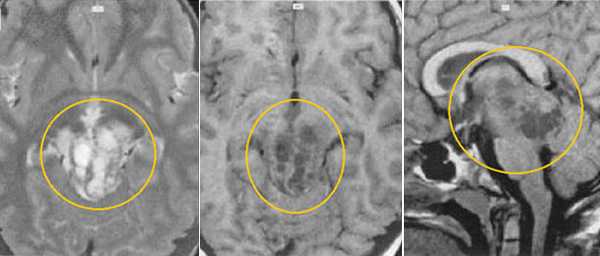

Пинеоцитома. МРТ в режиме Т2 и Т1 выявляется солидного строения опухоль задних отделов III желудочка мозга. На фоне в/в контрастирования определяется выраженный и достаточно гомогенный характер контрастирования опухоли.

Пинеобластома. В режиме Т2 и Т1 выявляется опухоль задних отделов III желудочка мозга с развитием окклюзионной гидроцефалии. В строме опухоли небольшой участок подострого кровоизлияния. После в/в контрастирования опухоль интенсивно и достаточно гомогенно накапливает контрастирующее вещество.